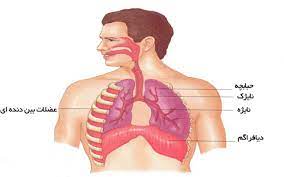

قیمت: 96٬000 تومان - دسته بندی فایل: علوم پزشکیپاورپوینت فیزیولوژی تنفسی (ppt) 123 اسلاید

فروش ویژه پاورپوینت حرفه ای فیزیولوژی تنفسی / تعداد اسلاید: 123 اسلاید